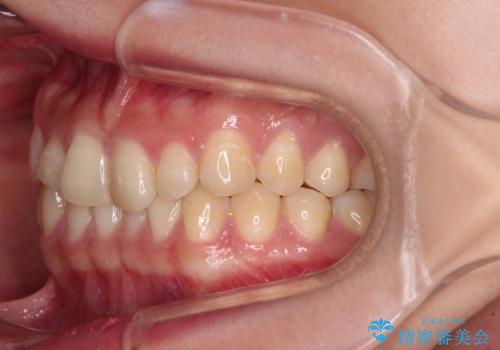

治療途中の奥歯と矯正治療の後戻り インビザライン・ライトによる矯正治療

- 根管治療を行ったままの奥歯と、矯正治療の後戻りを気にして来院された患者様です。

根管治療された歯に症状はなく、オールセラミッククラウンにて補綴治療を行うこととしました。

矯正治療の後戻りは軽微であったため、インビザラインの簡易パッケージであるインビザライン・ライトを用いて歯列を整えることとしました。

クラウンはよりよい咬み合わせで装着したいため、インビザラインを1セット使用して概ね歯列を整えた時点で補綴治療を行い、その後仕上げの矯正治療を行いました。